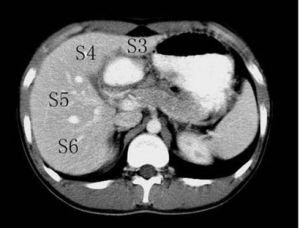

Couinaud根据门脉系统肝段按顺时针方向标以罗马数字从ⅠⅡⅢⅣⅤⅥⅧ,其中左内叶及尾状叶不再分段。 肝脏分8个段,主要被肝静脉系统和门静脉系统分割。肝中静脉将肝分成左右两叶。肝右静脉分肝右叶为右前、右后两部分。肝左静脉分肝左叶为左内叶、左外叶。门静脉系统走行于肝段内。Ⅰ段为尾状叶,CT示在门、腔静脉之间,Ⅱ段(靠上)与Ⅲ段(靠下)构成左外叶,Ⅳ段为方叶,也是左内叶,Ⅴ段(靠下)与Ⅷ(靠上)段构成肝右前叶,Ⅵ段(靠下)与Ⅶ段(靠上)构成肝右后叶。至于Ⅱ段与Ⅲ段、Ⅴ段与Ⅷ段、Ⅵ段与Ⅶ段分界,粗略方法以肝内门静脉分支或肝门平面为分界标志,出现以上平面所显示的是靠上方的,Ⅱ段、Ⅶ段、Ⅷ段,以下层面就是Ⅲ段、Ⅴ段、Ⅵ段。Ⅴ段与Ⅵ段、Ⅶ段与Ⅷ段之间以肝右静脉分界。影像学上横断面上以肝静脉为界,2,3;5,8;6,7 的分界大约门静脉左右分支平面。 医学百科网 | YxBaike.Com

1、肝脏分段的意义:可以了解病灶所处位置,尤其对于肝脏恶性肿瘤患者,从而指导治疗。肝脏的分段和肝脏的解剖密切相关,了解了肝脏的解剖并且应用到影像学的分析中去,也就可以熟练的了解肝脏的分段了。 2、分段主要依靠CT。 CT:首先找出肝脏的三大静脉:肝中静脉,肝左静脉,肝右静脉;找出门静脉及其分叉部位。门静脉分叉可以区分上段和下段,即肝S5/S8,S6/S7,门静脉分叉以上为S8,S7;肝右静脉和肝中静脉之间是右前叶,肝右静脉以后是右后叶;一般规律,从CT上看,最先看到的是S8,然后是S2、3,肝左外叶以肝裂为界,比较容易辨认,左内叶为肝裂和肝中静脉之间区域,胆囊往下的层次是S5,最后的层面一般是肝S6,下腔静脉和门静脉夹着的是尾状叶,即S1。